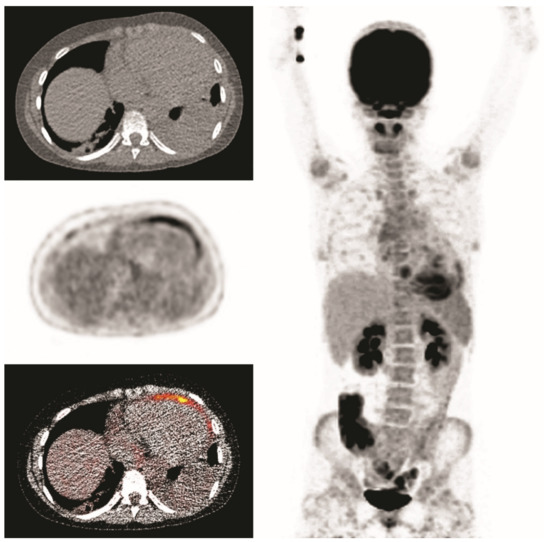

3.6. Clinical Examples